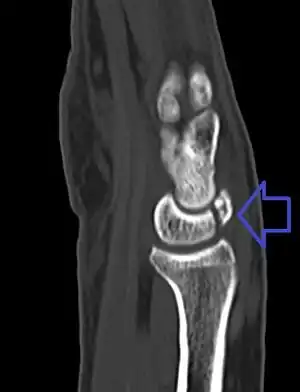

A lunate fracture as seen on CT scan of the wrist

The cause is often a fall onto the hand.[2] Types include palmar pole, distal pole, transverse, osteochondral, and transarticular body.[1] Diagnosis is typically confirmed by plain X-rays, CT scan, bone scan, or MRI.[1] Other conditions that may appear similar include Kienböck disease and congenitally bipartite lunate.[1]